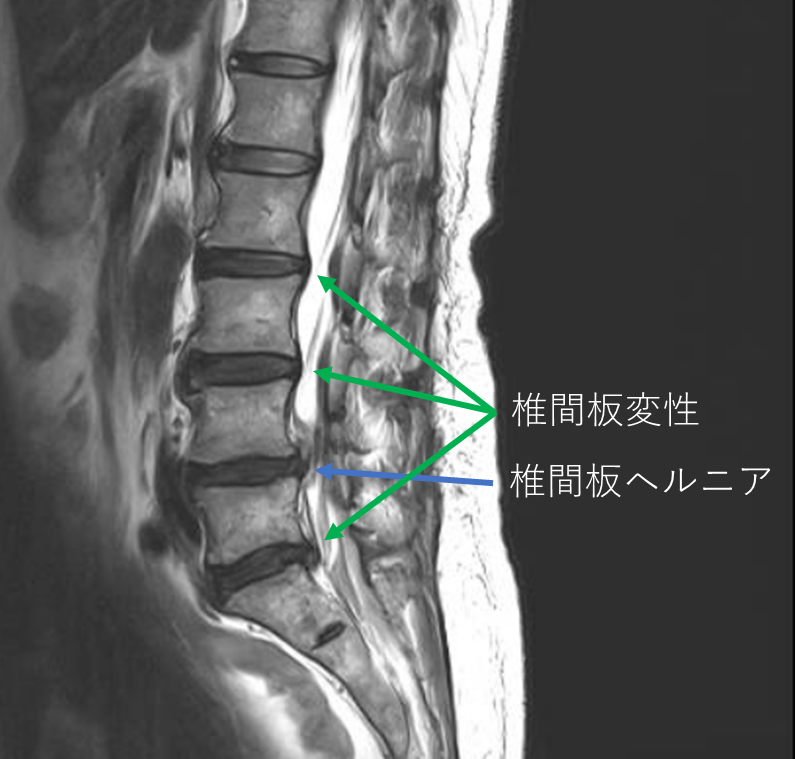

画像及び所見について

- L4/5-椎間板ヘルニア

- L2/3,3/4,4/5,5/s-椎間板変性症

以上の事が画像上認められます。

・L4/5-椎間板ヘルニアを認め、主症状の原因の可能性が高い

・L3/4,4/5-椎間板変性症を認め、予防的な意味合い